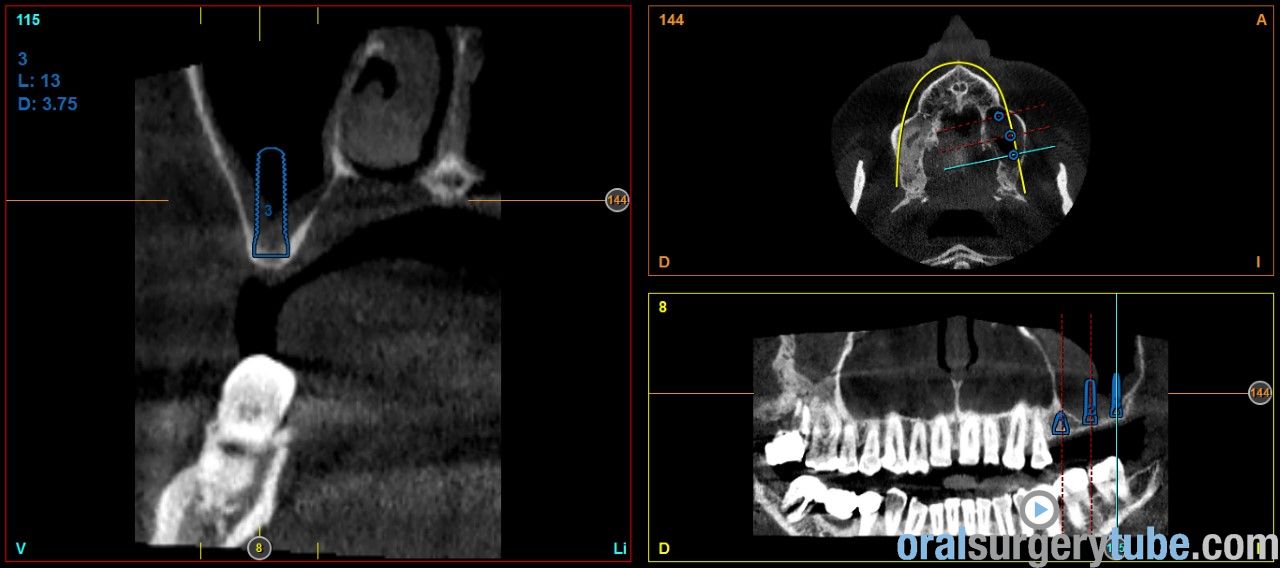

Engrosamiento mucoso

Estimados compañeros, me gustaria saber como abordaríais el seno izquierdo el cual como veis presenta engrosamiento mucoso. Haríais tratamiento previo? Gracias de antemano

Os envío imagenes. Se aprecia engrosamiento de la membrana del seno maxilar izdo.